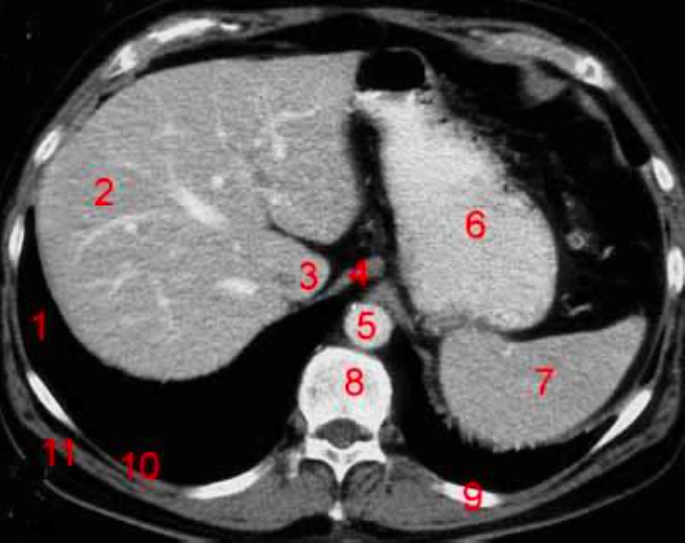

1

Q

Number 3?

A

IVC

2

Number 1?

R Kidney

3

How well did you know this?

4

Number 2?

5

Gall bladder

6

Number 8?

Body of thoracic vertebra

7

Number 9?

Lt rib

8

Number 7?

Unlabeled

9

Number 4?

Rectus abdominus

10

Descending colon

11

Rt lobe of liver

12

Number 10?

Rt rib

13

Head of pancreas

14

Rt diaghragmatic crus

15

Bowel (probably large)

16

17

Rt lobe liver

18

R lung

19

20

Number 6?

Stomach